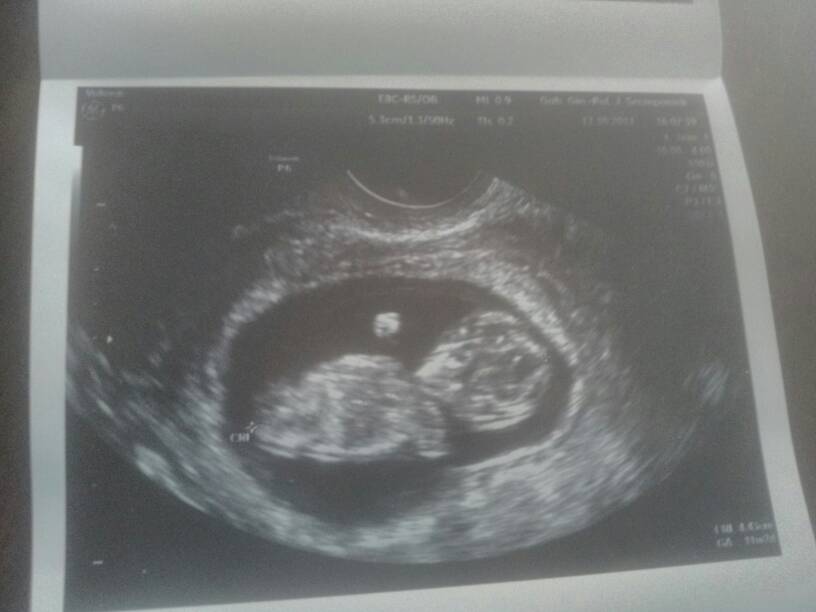

Ja juz po wizycie. Wszystko ok :) wyslala mnie na usg genetyczne co mnie troche dziwi bo jestem przed 30. *-*

1508252228-aaaaaa.jpeg